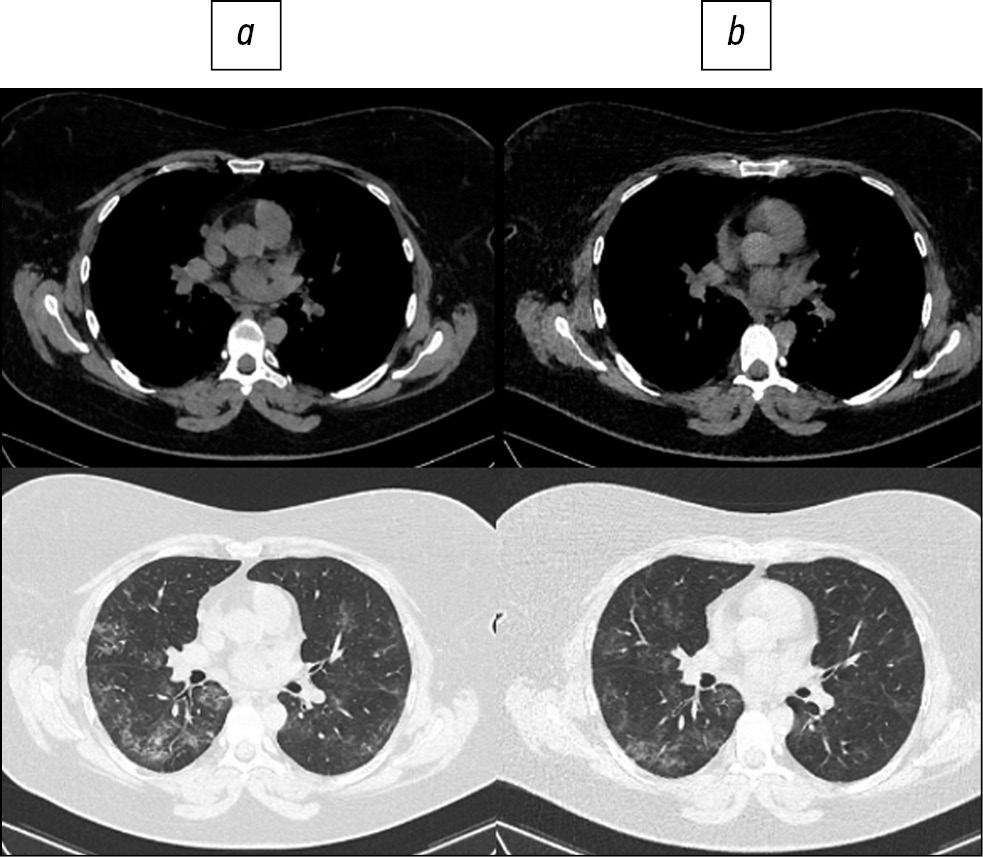

Fig. 4. Patient, 46 years old: standard computed tomography at admission was performed with a radiation dose of 5.6 mSv (a), low-dose computed tomography - 1.7 mSv (b).

Here are illustrative examples of clinical cases (Figs. 1–6), demonstrating the similarity of diagnostic value of two aforementioned research methods. Columns on the left (a) show images of a standard CT scan performed upon admission of the patient to the hospital, and columns on the right (b) present LDCT over time. The top line of images indicates the pulmonary window mode, whereas the bottom line indicates the mediastinal window mode. For comparison, values of radiation exposure in each case are presented. Time intervals between standard CT and LDCT were 2–7 days; thus, the primary endpoint was reached in all patients enrolled in the study.